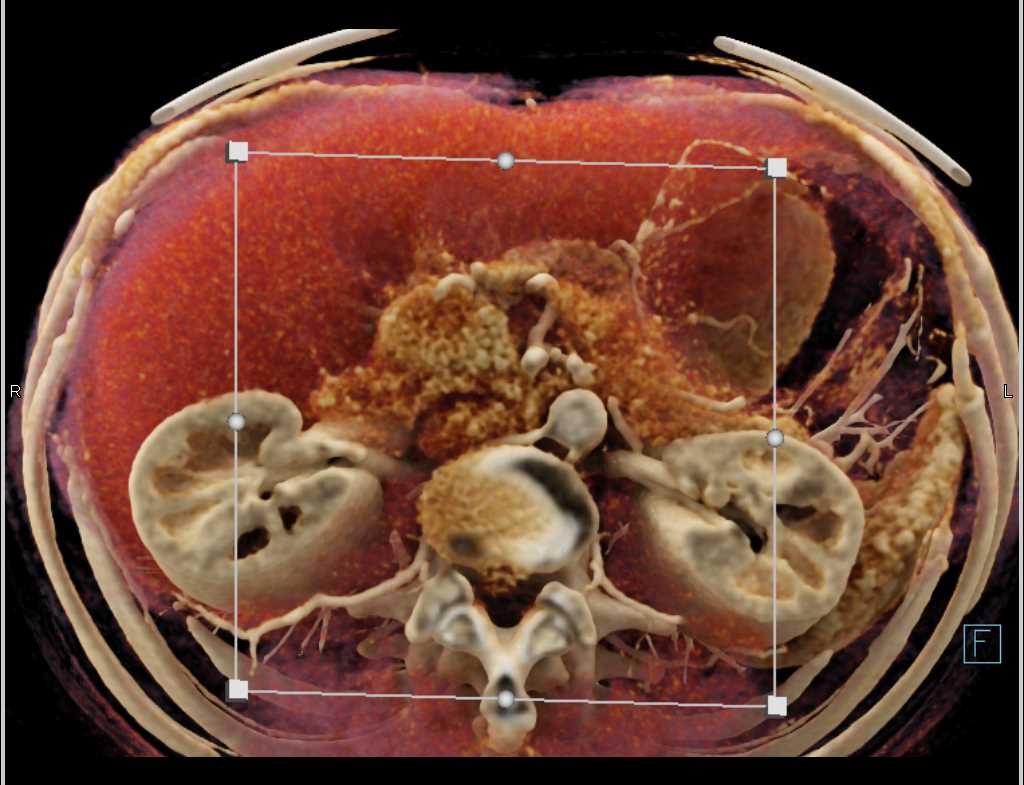

Intraductal Papillary Mucinous Neoplasm (IPMN) with High Grade Dysplasia